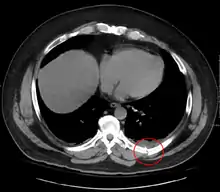

معرض صور